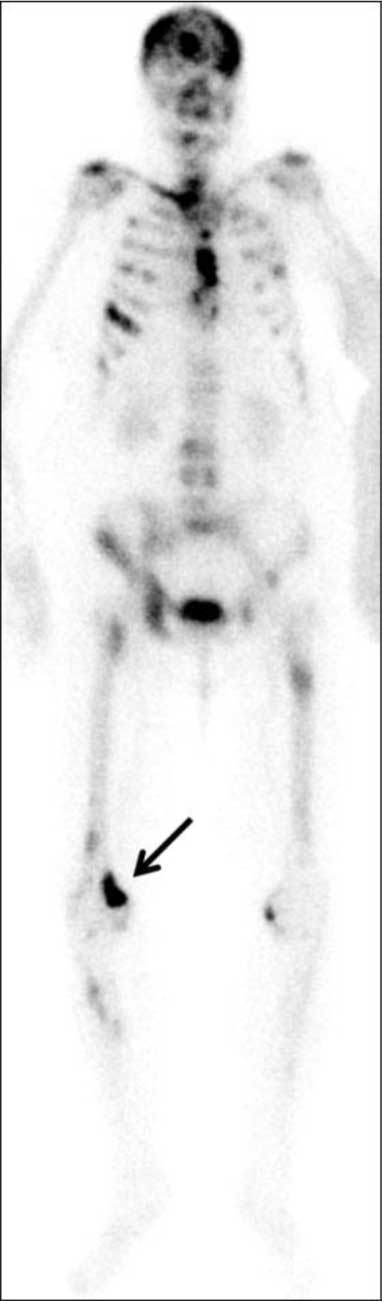

Figure 2

Skeletal scintigraphy – corresponding metabolically active lesion in the right femur (arrow) and multiple other widespread skeletal metastases.